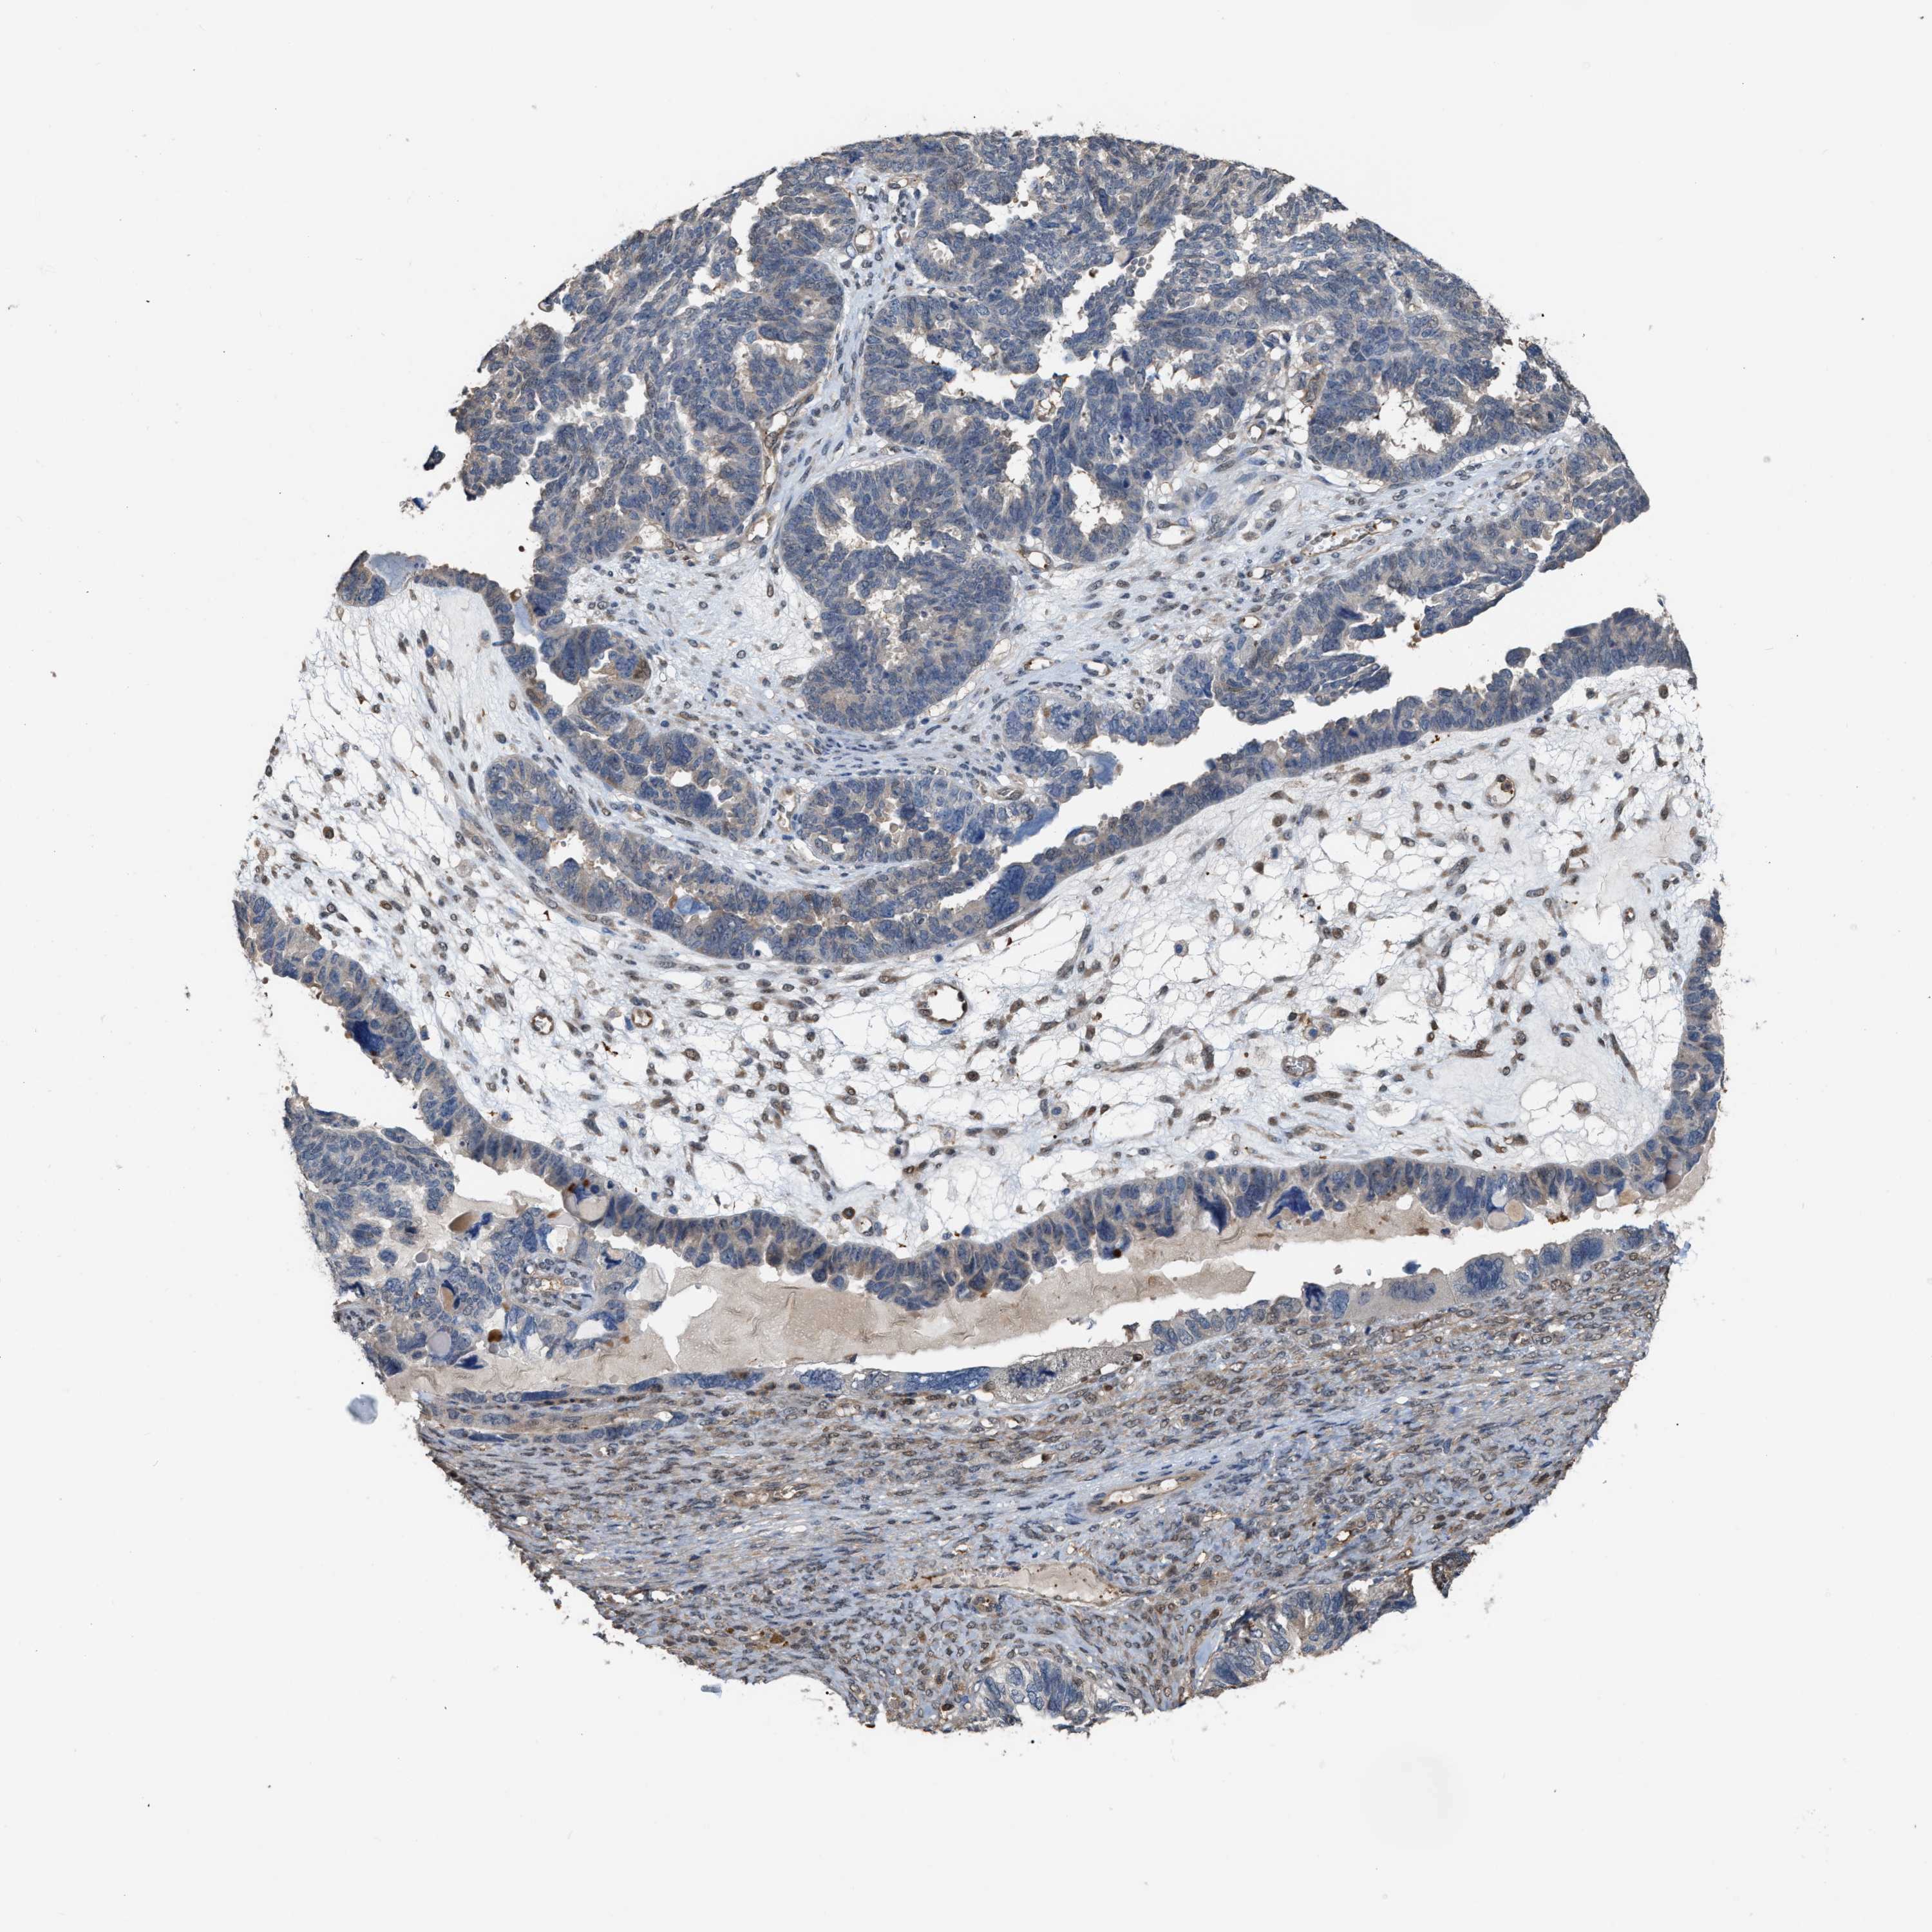

OVARIAN CANCER - Protein expressioni

A mouse-over function shows sample information and annotation data. Click on an image to view it in a full screen mode. Samples can be filtered based on level of antibody staining by selecting one or several of the following categories: high, medium, low and not detected. The assay and annotation is described here.

Note that samples used for immunohistochemistry by the Human Protein Atlas do not correspond to samples in the TCGA dataset.

Antibody stainingi

Antibody staining in the annotated cell types in the current human tissue is reported as not detected, low, medium, or high, based on conventional immunohistochemistry profiling in selected tissues. This score is based on the combination of the staining intensity and fraction of stained cells.

Each image is clickable and will lead to virtual microscopy that enables deeper exploration of all samples and also displays staining intensity scores, fraction scores and subcellular localization as well as patient and tissue information for each sample.

Antibody HPA019735

Staining

High

Medium

Low

Not detected

Intensity

Strong

Moderate

Weak

Negative

Quantity

>75%

75%-25%

<25%

None

Location

Nuclear

Cytoplasmic/membranous

Cytoplasmic/membranous,nuclear

Cystadenocarcinoma, serous, NOS

Carcinoma, endometroid

Cystadenocarcinoma, mucinous, NOS

Carcinoma, NOS